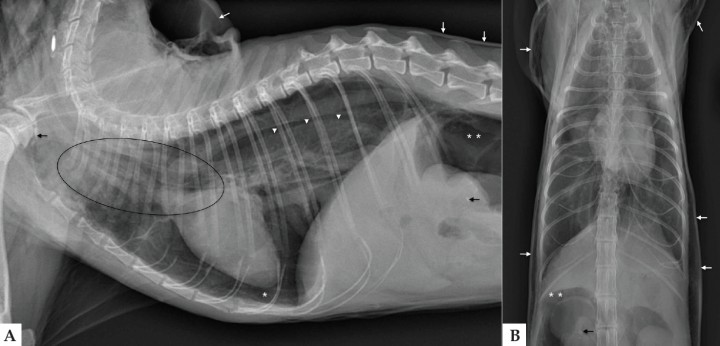

El análisis de sangre no reveló anomalías significativas. Se realizaron radiografías lateral derecha y ventrodorsal de la cavidad torácica (Fig. 1).

Radiografías de tórax en proyección lateral derecha (A) y ventrodorsal (B) en un gato Persa de 15 años con un cuadro de disnea y enfisema subcutáneo.

En la proyección lateral derecha del tórax (Fig. 2A) se observa una mejor visualización de las estructuras mediastínicas craneales, incluyendo la pared traqueal, el esófago y los vasos sanguíneos, al aparecer rodeadas por gas. Los hallazgos son sugerentes de neumomediastino. También se observa desplazamiento dorsal de la silueta cardiaca por una banda de opacidad gas y retracción del lóbulo pulmonar caudal, compatible con neumotórax. Hay aumento de la densidad radiológica del pulmón, posiblemente por atelectasia pulmonar secundaria.

Mismas imágenes que en Figura 1. Proyección lateral de tórax (A): Neumomediastino (elipse); neumotórax (asterisco blanco) con retracción del lóbulo pulmonar caudal (cabeza de flechas blancas); enfisema subcutáneo (flechas blancas) y neumoretroperitoneo (doble asterisco blanco). Osteofitos o artrolitos a nivel de las articulaciones escapulohumerales y pequeñas mineralizaciones a nivel de las siluetas renales (flecha negra). En la proyección ventrodorsal (B) realizada tras drenaje del neumotórax se observa mayor distensión pulmonar.

Se aprecia gas en la región del cuello que se extiende a lo largo de la pared torácica y abdominal, compatible con enfisema subcutáneo, así como en área retroperitoneal craneal, indicativo de neumoretroperitoneo. Como hallazgos incidentales se visualizan osteofitos o artrolitos a nivel de las articulaciones escapulohumerales, compatible con osteoartrosis, y pequeñas mineralizaciones a nivel de las siluetas renales.

Tras el drenaje del neumotórax se realiza la proyección ventrodorsal (Fig. 2B), ya que la disnea que presentaba el paciente previamente dificultaba realizar proyecciones adicionales. En la imagen se puede observar una mayor distensión pulmonar.